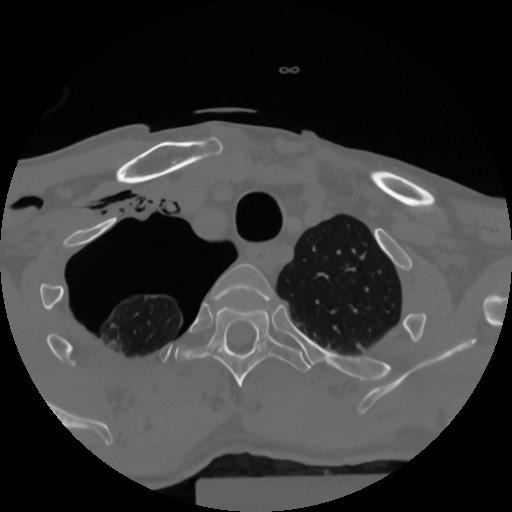

12 P.BLANDAS,,Vol,0.5,P.BLANDAS,,